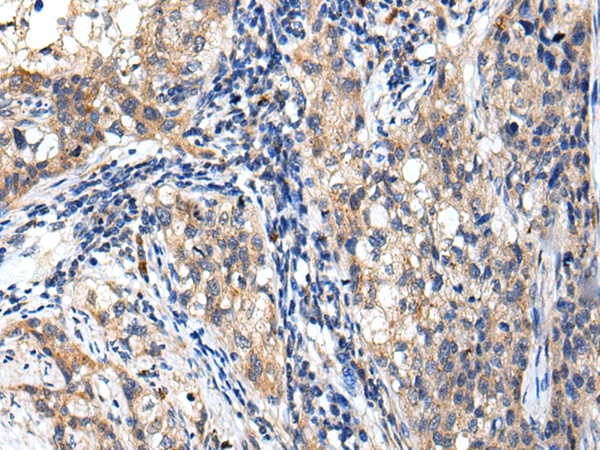

The image is immunohistochemistry of paraffin-embedded Human prostate cancer tissue using (RNF141 Antibody) at dilution 1/25. (Original magnification: ×200)

The image is immunohistochemistry of paraffin-embedded Human lung cancer tissue using (RNF141 Antibody) at dilution 1/25. (Original magnification: ×200)